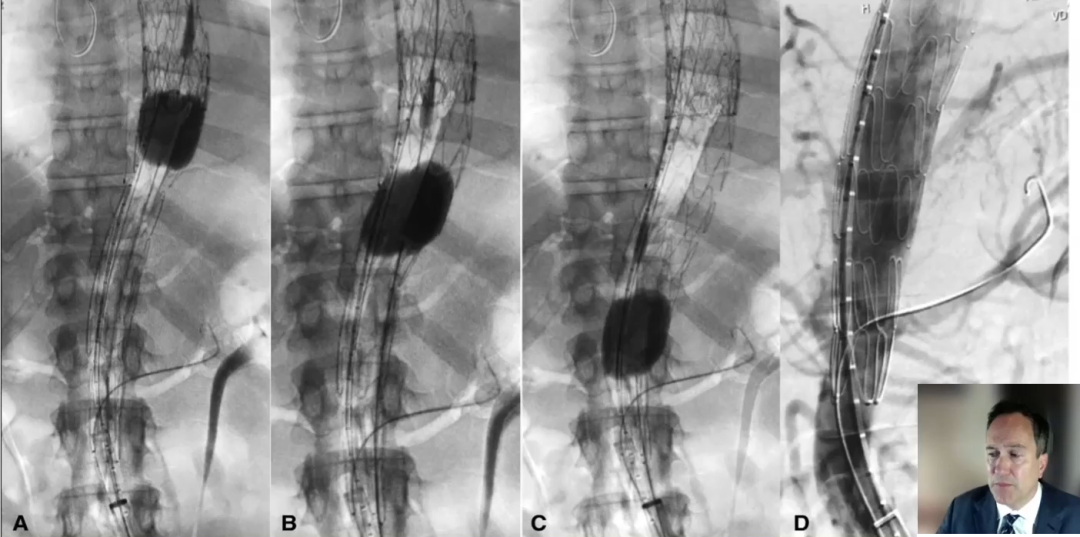

根据下图中的操作细节和结果可以得到的信息为:从出现症状到STABILIZE手术的间隔时间是9个月,可以看到使用球囊对覆膜支架下方的裸支架进行后扩张,改善贴壁并获得更好的定位。

根据下图数据,可以看到STABILIZE技术一个显著的并发症,也是我们必须要注意的地方:在球囊扩张过程中(不能在大于42毫米的远端动脉瘤上进行),会出现假腔血栓远端迁移。可能是因为影响了部分附壁血栓,并使其向远端移动。

(9个月的平均数据图)